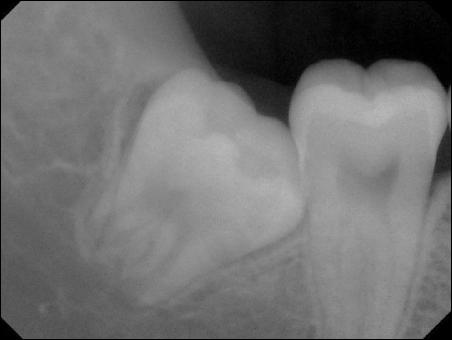

由于人類的進(jìn)化,上下頜骨沒有更多的空間留給我們長牙,因此,智齒經(jīng)常的會長不好,容易出現(xiàn)阻生的情況。什么是阻生,就是阻礙生長。智齒以不同的方式阻礙前牙(第二磨牙,第7顆牙)的生長,從而導(dǎo)致經(jīng)常的發(fā)炎,也就是智齒冠周炎。大家看下面這張圖:

典型的垂直阻生狀況